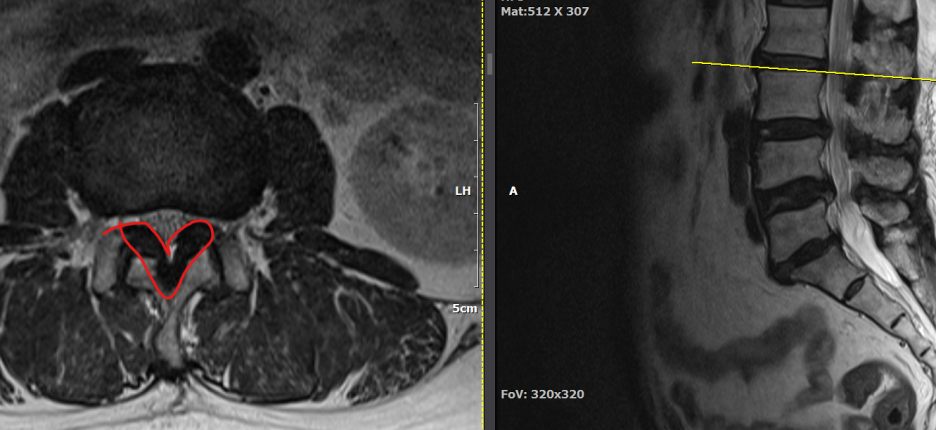

척추관 협착증은 척추관이 좁아지거나 협착되어 척수나 신경근을 압박하는 상태를 말합니다. 이런 경우, 양방향 척추 내시경이 매우 유용한 치료 수단이 될 수 있습니다.

- 계획: 양방향 척추 내시경은 미세한 카메라와 도구를 사용하여 척수와 주변 신경 구조를 정밀하게 시각화할 수 있습니다. 이를 통해 정확한 진단을 내릴 수 있으며, 각 환자에게 맞는 개별적인 수술 계획을 수립할 수 있습니다.